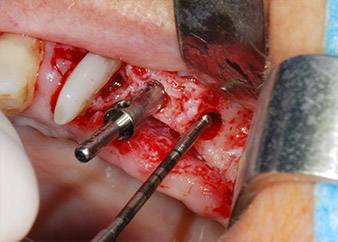

implant motor

Fig. 8: Rotary preparation of the implant bed short of the floor of the maxillary sinus at position 25, carried out with an updated implant motor.

Implant beds were prepared at sites 25 and 26 with rotary instruments, used in a contra-angle handpiece with a 20 : 1 transmission ratio with an updated powerful implant motor (Implantmed, W&H) (Fig. 8).

The final preparation next to the sinus was again carried out with a piezoelectric instrument (Piezomed, insert S2).